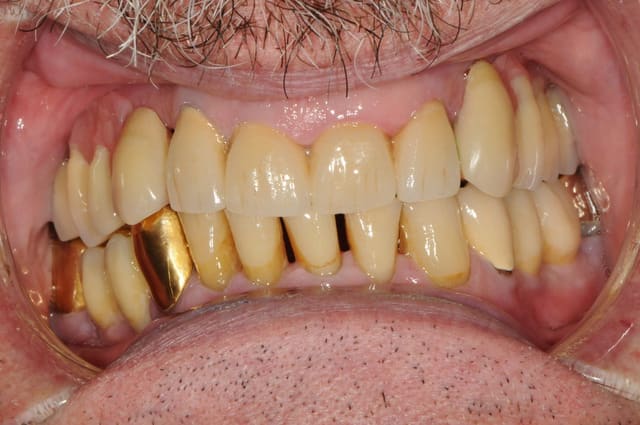

au final, c'est un patient heureux avec un stellite super stable.

enfin des céramiques esthétiques et adaptées à l'âge du patient. Super.

Sur la photo "5658", il y a rougeur importante sur la

crête/gencive. Je crois que ton occlusion est trop forte. Dommage qu'il manque un appui plus postérieur dans ce coin.

L'ensemble st quand même très bien.

mais non, c'est une photo avant juste avant la pose du nouvel appareil. ici, la gencive est un peu traumatisée par le vieux partiel résine qui servait de cache misère.